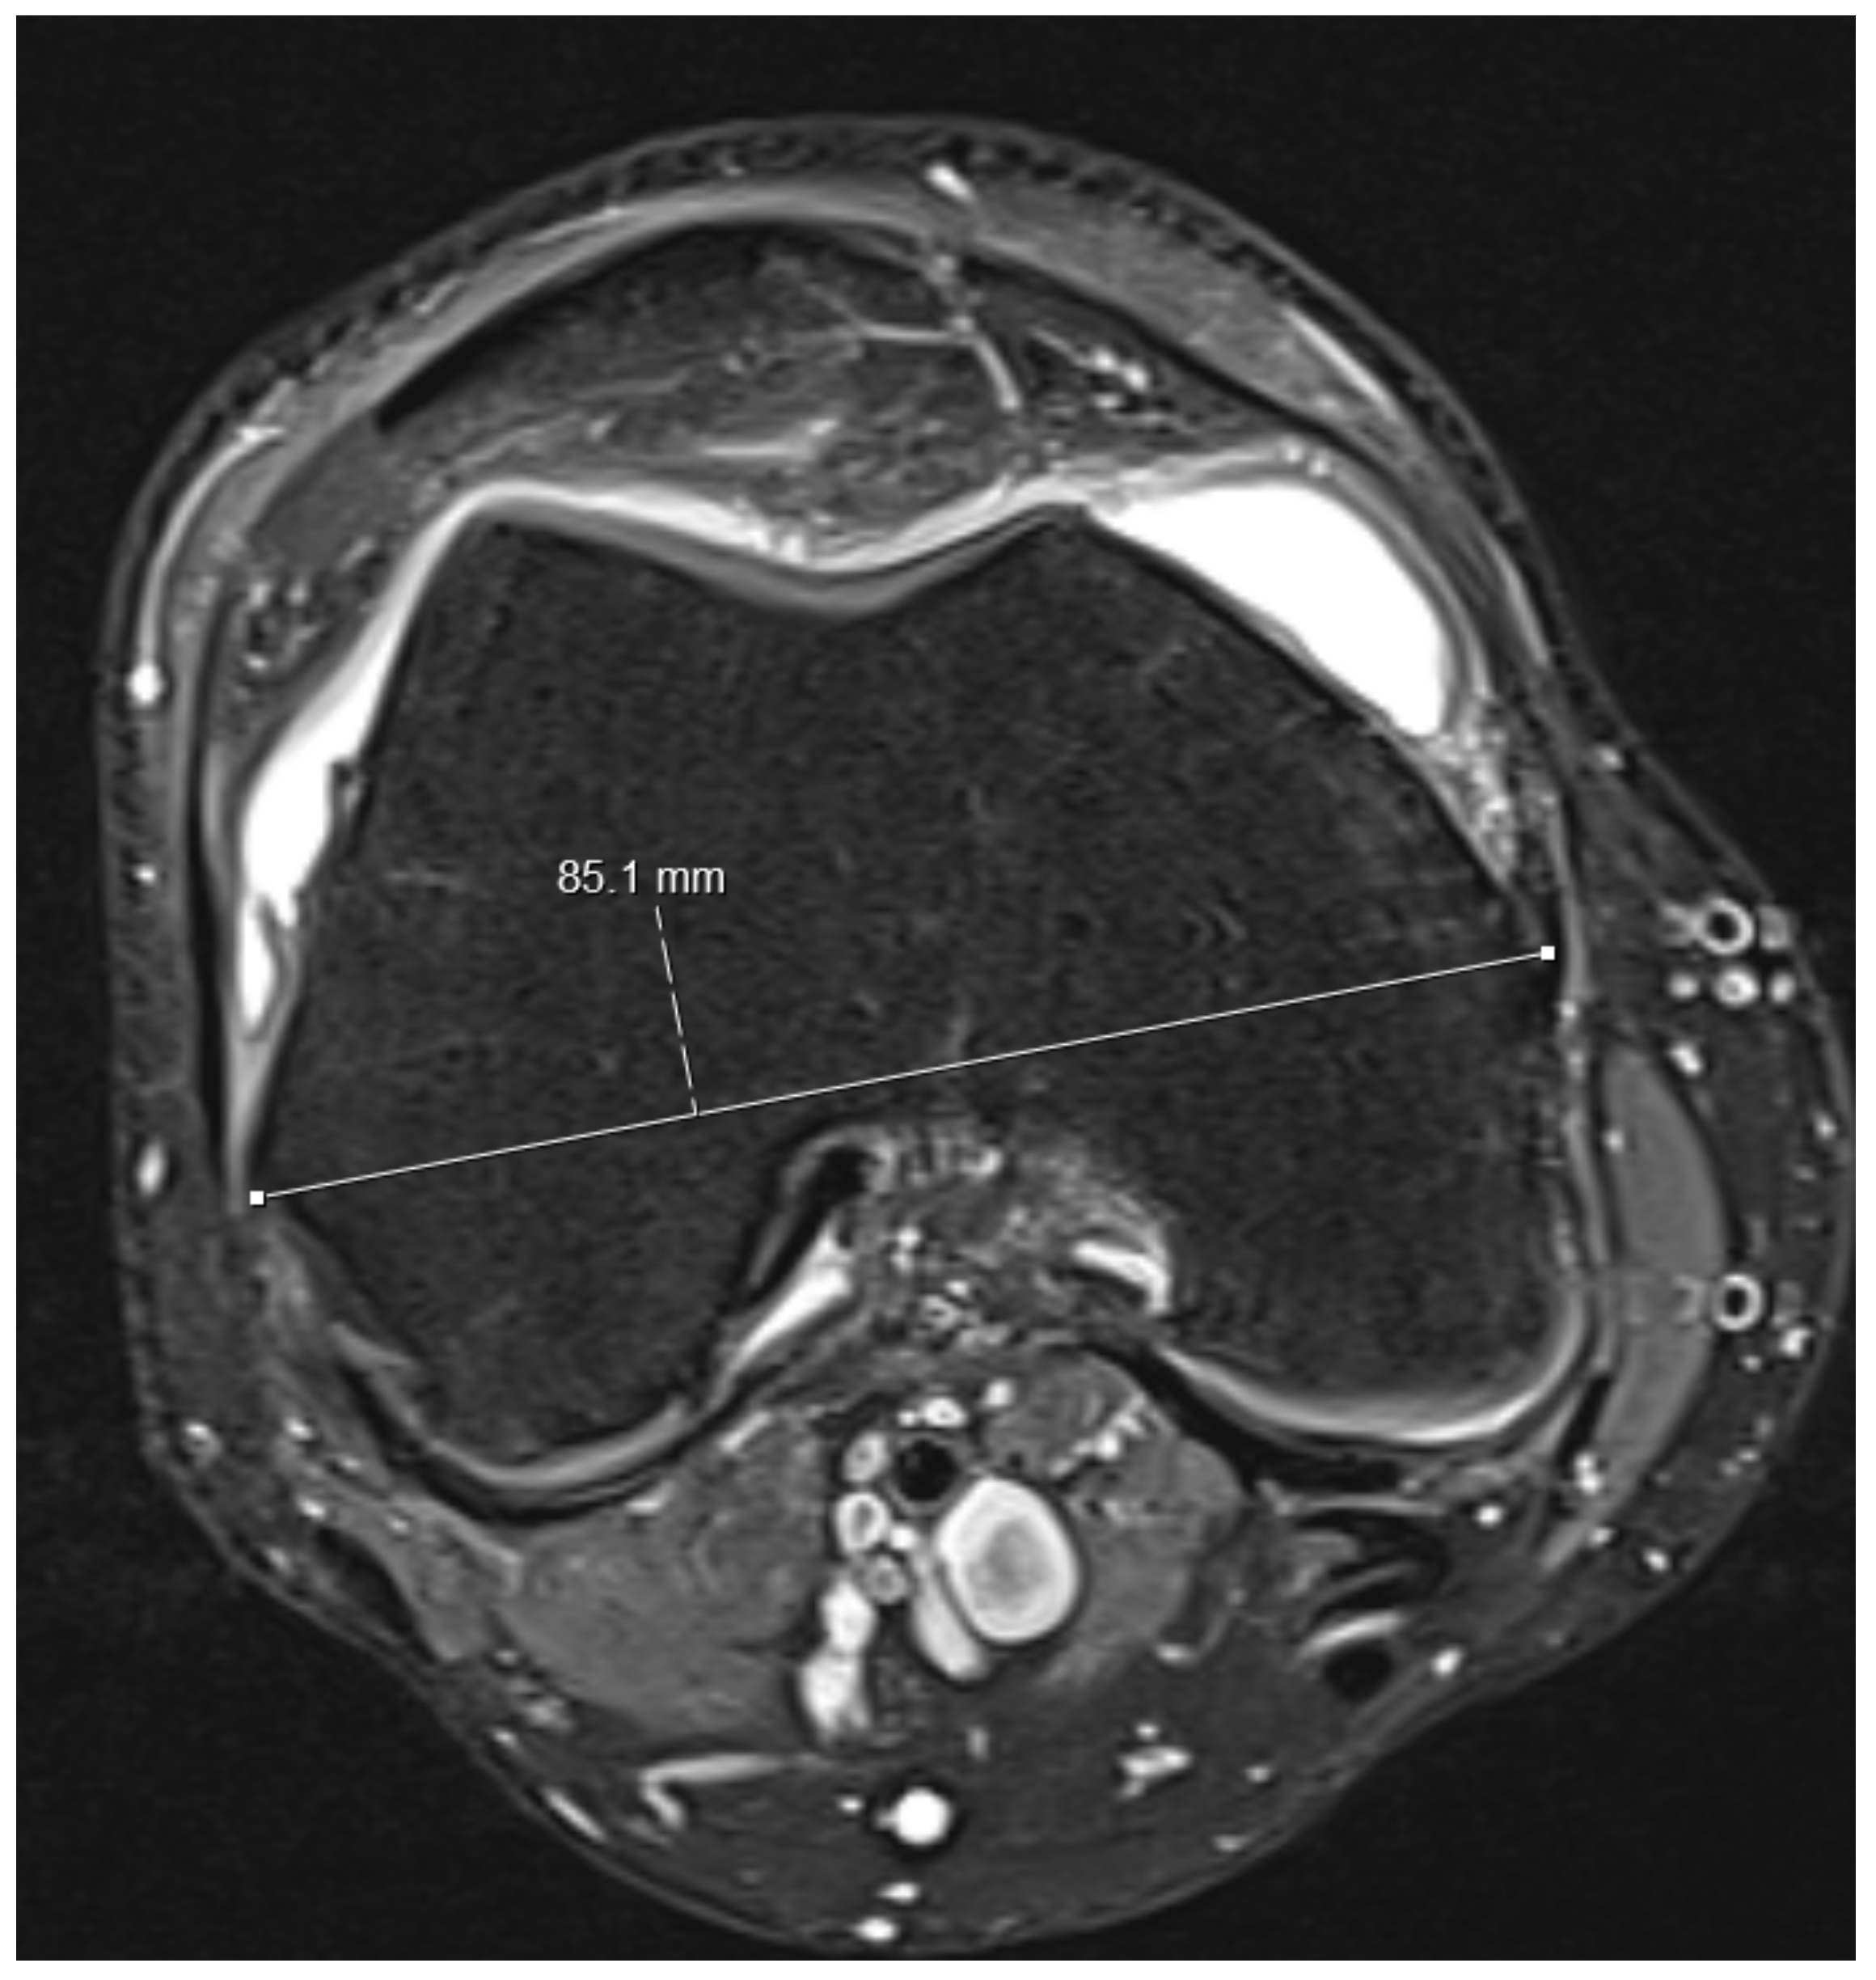

- Knee diameters were measured on axial PD-weighted images at the exact level of the patella upper pole (strictly antero-posterior = vertical, and medio-lateral = horizontal, independent of the leg position; Figure 2). The larger of these 2 diameters was taken as “maximal diameter”.

- The whole knee cross-sectional area at the same level was automatically calculated by the Osirix software (Figure 2),